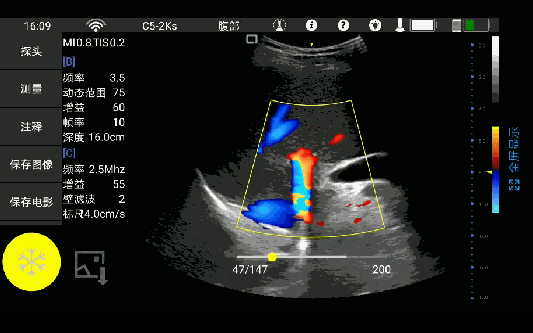

• 大凸

腹部

肾脏

妇科产科

心脏

肺等